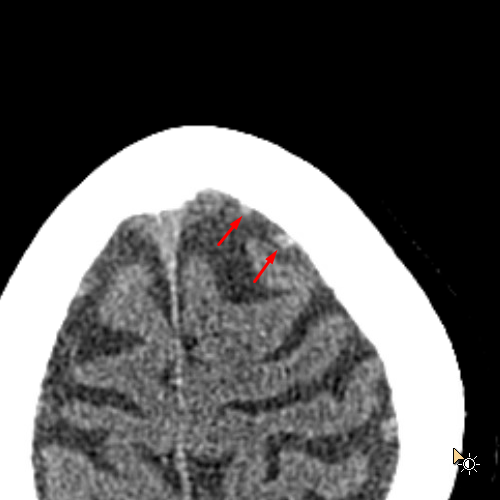

Age: 84

Sex: Female

Indication: Fall on anticoagulation